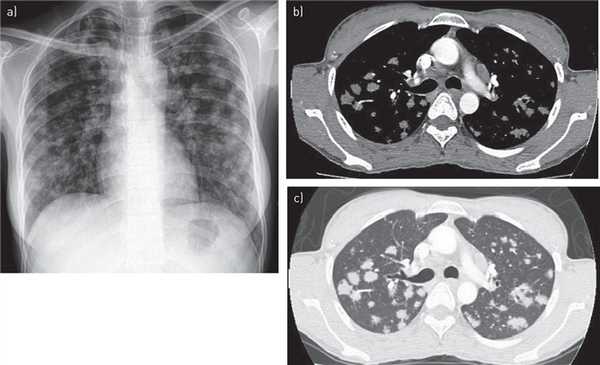

Центрилобулярные (ацинарные) узелки

Центрилобулярные (ацинарные) узелки - узелки нечёткой плотности, в среднем, размерами от 5 до 10 мм, зачастую сочетающиеся с альвеолярной консолидацией, располагающиеся вокруг периферических бронхов и бронхиол, в центре легочной дольки (вторичная легочная долька). Выявляются при долевых пневмониях, эндбронхиальном распространении инфекции (в частности туберкулёза) - в виде признак дерева в почках (tree-in-bud) и бронхоальвеолярной карциноме.

О характере распределения можно судить только при компьютерной томографии.

Дифференциальный диагноз

- бронхиолит

- эндбронхиальном распространении инфекции

- нетуберкулезная микобактериальная инфекция

- Черджа-Стросс синдром